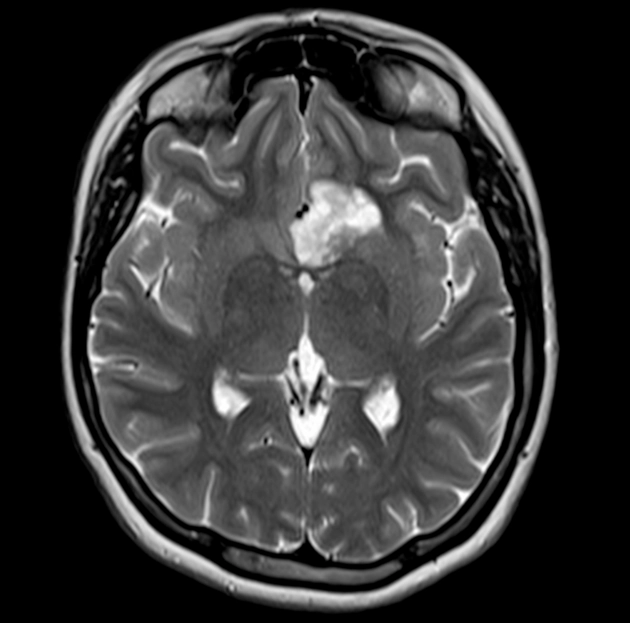

Di căn nhu mô não (Parenchymal metastases)